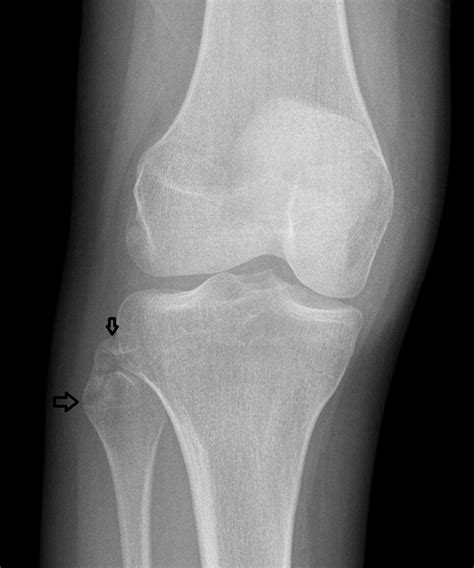

Diagnosis of Proximal Fibula Fracture

Diagnosing a Proximal Fibula Fracture involves a combination of physical examination and imaging tests. The diagnostic process typically includes:

• Physical examination: A healthcare provider will assess the injured area for pain, swelling, and deformity.

• X-rays: Imaging tests to visualize the bone and determine the location and severity of the fracture.

• CT scans or MRI: In some cases, more detailed imaging may be required to assess the extent of the injury and plan treatment.